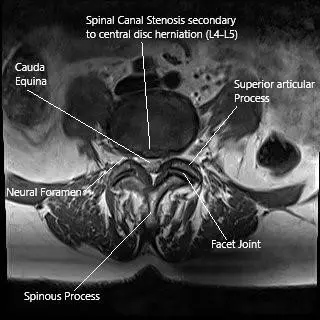

MRI of the Lumbar spine in axial section central disc herniation.

• MRI: The gold standard for diagnosing disc herniation, nerve compression, or soft tissue abnormalities.